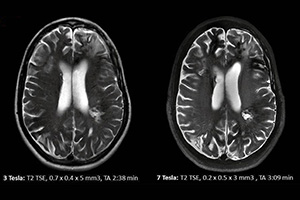

1993 Yılından bu yana İstanbul’da Tanı hizmeti veren Star-Test, teknoloji ürünü en gelişmiş radyolojik cihazlara sahip olup